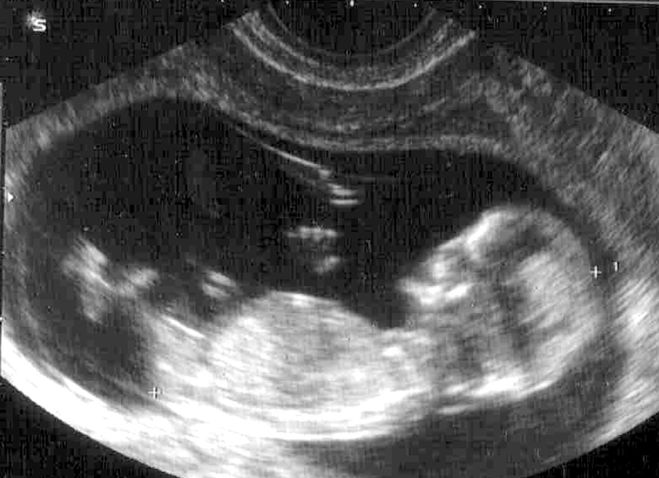

Какие фото УЗИ и живота на 12 неделе беременности? Какой вес и рост плода? - Рой пчел Ответы на все любые вопросы